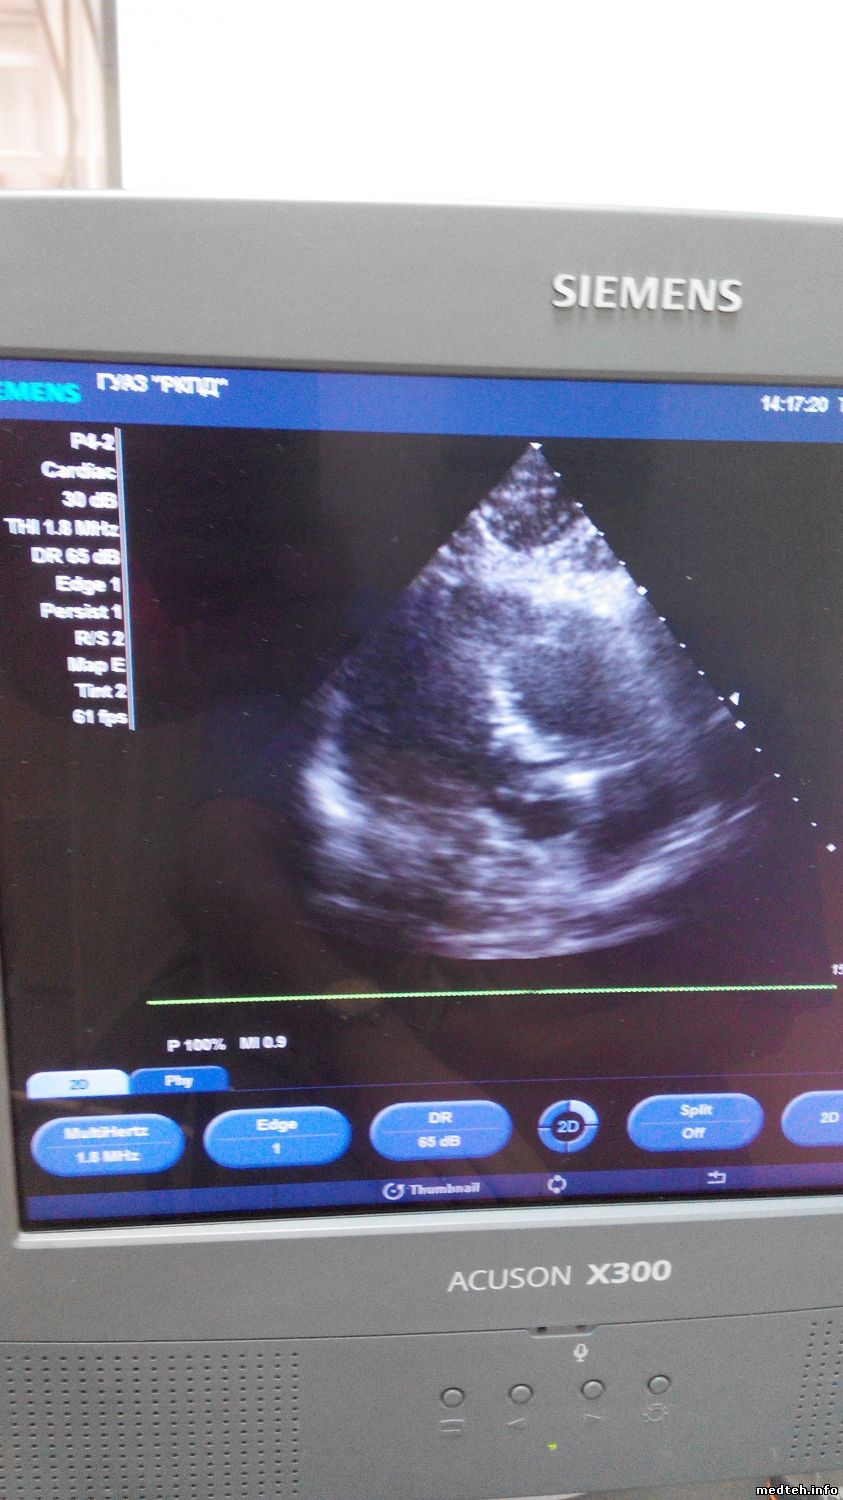

Итог: С подменными от моего не исправного УЗИ результата не дало, мои 2 секторных датчика Р4-2 и Р8-4 на том аппарате работают хорошо!!!!!!!!!! unknown

А на моём УЗИ, эти же датчики, при сердечном кровотоке ШУМЯТ!!!! ПОМЕХИ и прочую паразитивную гадость показывают!!!!!!!!!!!

Вот фото с помехами, я настроил чувствительность так, что я даже не дотрагиваюсь до них, а картинка КОШМАРНАЯ!!!!!!

А вот как ведут эти же датчики на исправном УЗИ аппарате:

Без помех- строго по делу!!!